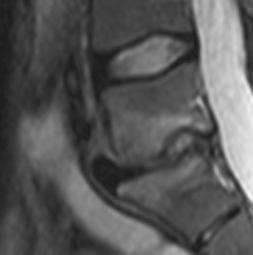

Discopathie MODIC 1 évoluant en MODIC 2. Notez le respect des corticales et l'absence de prise de contraste discale, malgré le franc hypersignal T2 du disque. Evolution à 1.5 ans en discopathie MODIC 2